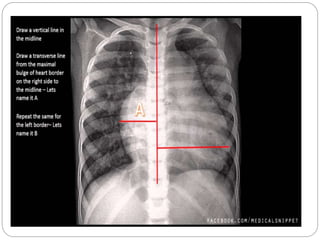

IMAGING STUDIES

 Chest roentgenography :

Cardiomegaly, pulmonary congestion, and

other findings consistent with heart failure

may be seen on chest radiography.